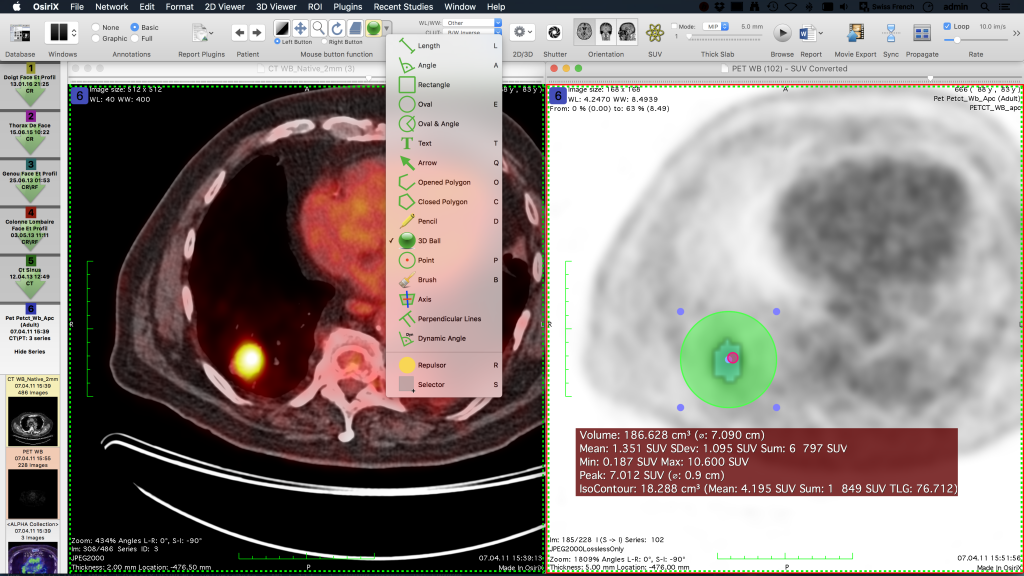

Çizgiler, çokgenler, 3B top gibi görüntülere Anahtar Görüntüler ve İlgi Alanları (ROI’ler) kolayca ekleyebilir ve bunları veritabanına kaydedebilirsiniz.

OsiriX MD, kardiyak veya perfüzyon alımları gibi 4D görüntüleri ve PET-CT görüntüleri gibi parametrik görüntüleri destekler.